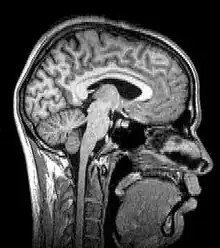

Tomography is imaging by sections or sectioning that uses any kind of penetrating wave. The method is used in radiology, archaeology, biology, atmospheric science, geophysics, oceanography, plasma physics, materials science, cosmochemistry, astrophysics, quantum information, and other areas of science. The word tomography is derived from Ancient Greek τόμος tomos, "slice, section" and γράφω graphō, "to write" or, in this context as well, "to describe." A device used in tomography is called a tomograph, while the image produced is a tomogram.

Although MRI (magnetic resonance imaging), optical coherence tomography and ultrasound are transmission methods, they typically do not require movement of the transmitter to acquire data from different directions. In MRI, both projections and higher spatial harmonics are sampled by applying spatially varying magnetic fields; no moving parts are necessary to generate an image. On the other hand, since ultrasound and optical coherence tomography uses time-of-flight to spatially encode the received signal, it is not strictly a tomographic method and does not require multiple image acquisitions.

| Magnetic resonance imaging or nuclear magnetic resonance tomography | Nuclear magnetic moment | MRI or MRT | |